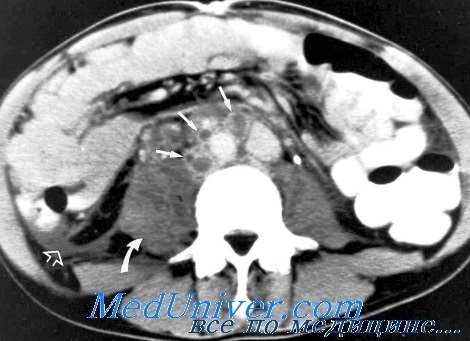

КТ забрюшинных лимфоузлов при лимфогранулематозе

Поражение брюшины и сальника характеризуется утолщением брюшины за счет инфильтрации ее на значительном протяжении. При этом теряется четкость брюшины, не дифференцируются структуры стенки живота и жировой клетчатки.

Сальник имеет вид плотного (36-48 HU) ограниченного образования, прилежащего к брюшине. Границы его местами нечеткие. Лимфатические узлы брыжейки тонкой кишки, брюшной аорты увеличены, а форма их поражения представлена конгломератом, инфильтратом, реже пакетом.

Поражение кишечника чаще встречается в правой половине толстой кишки и характеризуется значительным утолщением стенок (до 5 мм и более) с концентрическим сужением просвета. Наружный контур кишки нечеток в связи с распространением опухолевой ткани за пределы органа, вовлечением окружающей клетчатки и брыжейки. Лимфатические узлы толстой кишки поражаются в форме одиночных узлов, реже в форме пакета.